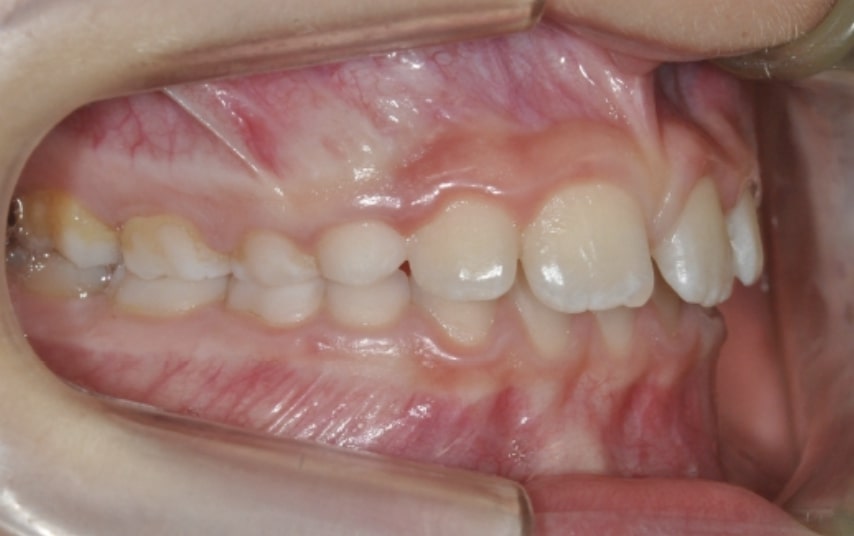

Malocclusion A6 Correction of Mandibular Retrusion in Growth phase patient | Skeletal Class II | Class II Division 1 malocclusion | Deep bite | Mixed dentition

Clinical examination and diagnosis

FUNCTIONAL: Suction of the lower lip and Labial incompetence.

FACIAL: class 2 profile with Lower jaw deficit

SOFT TISSUES ANALYSIS: Upper Frenulum with low insertion

SKELETAL PATERN: Class 2

DENTAL:

• Molar and Canine class 2 on the right side – Molar and Canine clss 1 on the left side

• Upper diastema (11-21)

• Increased Overjet

• DeepBite

• Reduced Transversal Diameters

• Deviated Lower Midline 2 mm to the Right